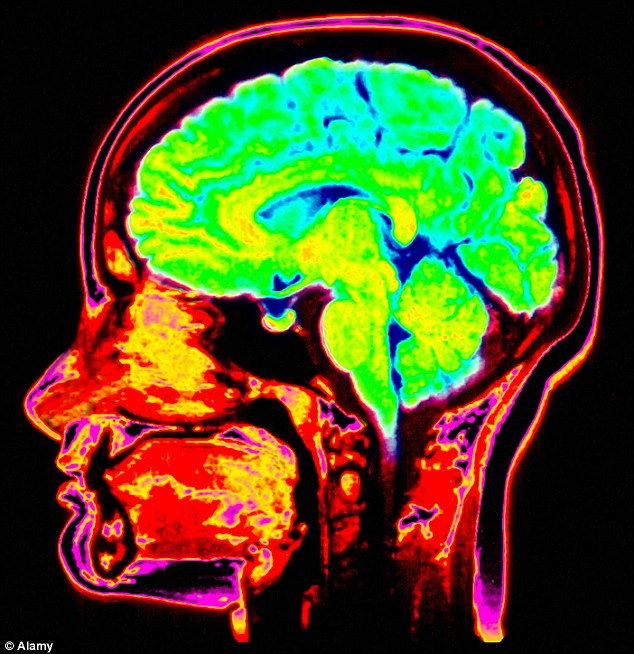

Hulumtuesit në universitetin “Columbia Medical Center” shqyrtuan funksionimin e trurit të një personi të ri dhe trurin e një moshe të vjetër.